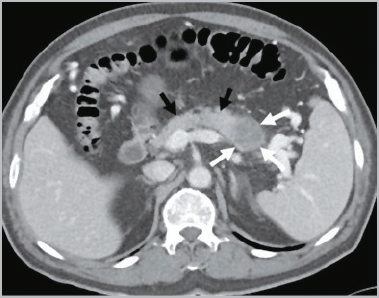

췌장은 위의 끝과 배꼽 사이 상복부에 위치한 소화기관으로 각종 소화효소와 인슐린을 분비하여 장내 음식물을 분해하고 혈당을 조절합니다. 췌장은 십이지장과 연결되어 있기 때문에 분비된 소화효소는 십이지장으로 방출되어 위에서 음식물과 섞이게 됩니다. 췌장은 해부학적으로 머리, 몸통, 꼬리로 나뉩니다.

머리는 담관과 연결되어 있기 때문에 머리에 있는 췌장암이 담관을 막아 황달을 유발할 수 있습니다. 꼬리는 비장과 연결되어 있습니다. 소장과 결장의 일부에 혈액을 공급하는 상부 장간막 동맥은 대동맥에서 분기되어 췌장 근처를 여행합니다.